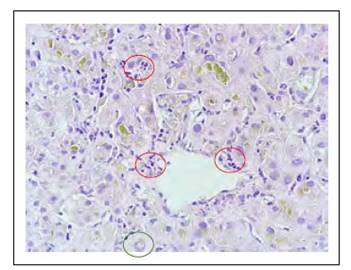

Los hallazgos histológicos en la biopsia hepática se muestran en las Figuras 1 a 6.

Figura 3 Necrosis focal en zona 3 (círculo rojo), algunos hepatocitos muestran núcleo glucogenado (círculo verde).

Figura 4 Colestasis intracanalicular e intracitoplasmática a predominio de la zona acinar 3. Ocasionales cuerpos apoptóticos (círculo rojo).